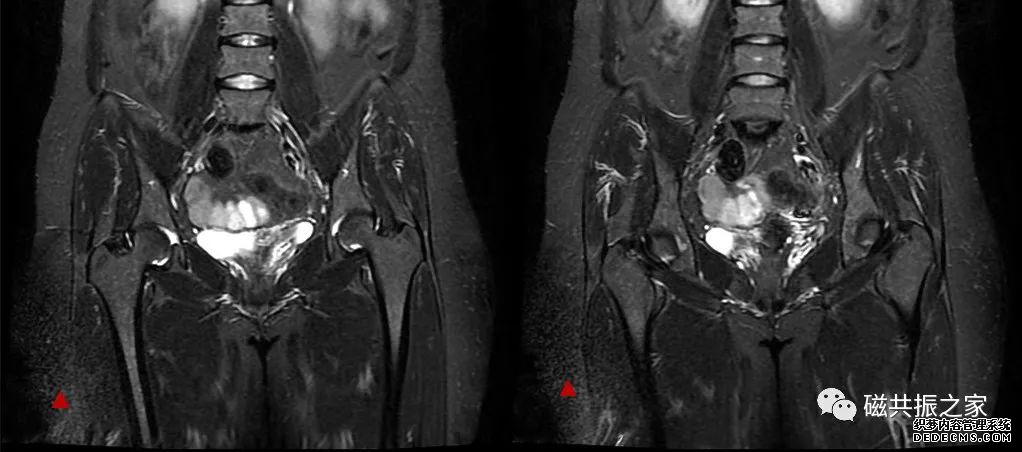

如上图△,在一例髋关节的扫描中,其8ch body fullfov线圈获得的校准图像的右侧局部区域的信号强度明显不及左侧,是线圈的问题还是某些因素的干扰所致。我们再看看BODY获得的校准图像,下图▽。

在同样的区域,BODY获得的校准图像左右侧的信号并无明显的差异,所以基本可以锁定是线圈的问题,最终获得扫描图像如下图▽。

获得的图像右侧下部局部区域信噪比较差,最终证实是8ch body fullfov线圈的右下单元的问题。在辨别线圈本身问题还是其它原因对图像造成的影响方面,利用校准序列来辨别是一个非常实用、有效的途径。